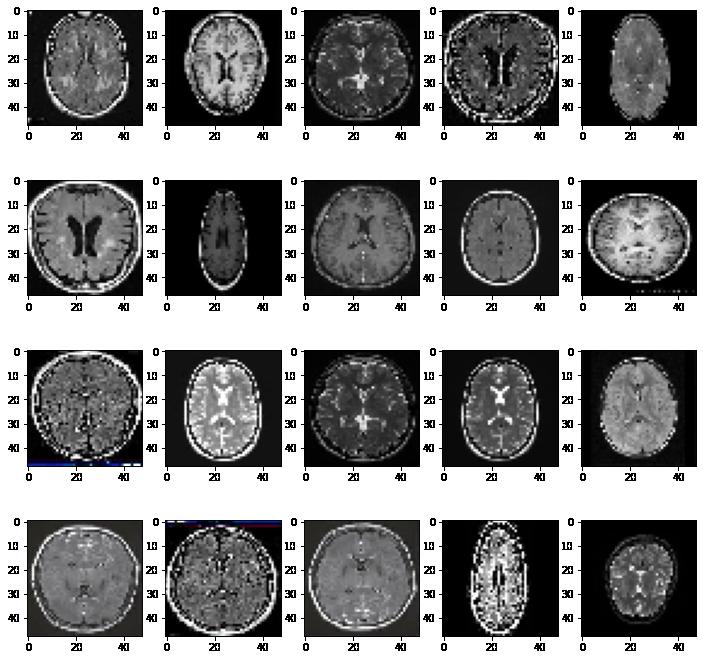

Visualizing MRI scans showing tumors

First, we are visualizing MRI scans that exhibit the presence of a tumor.

Visualizing MRI scans without tumors

Then let's see what MRI scans of healthy brains look like.

Observations:

The MRI scans of brains that have tumors have patches (white or gray) of varying sizes and they are present at different locations within the cross-sectional view of the brain.

The MRI scans of healthy brains show no such patches.